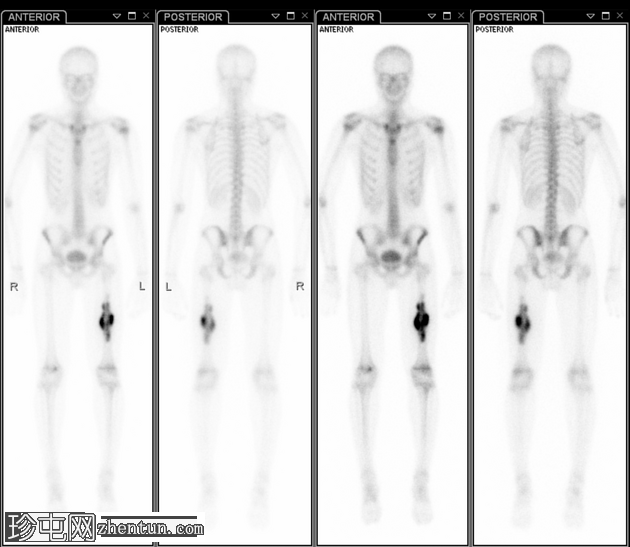

核

医学

检查

左股骨中1/3处可见明显的骨性及周围软组织摄取增多。

胸骨-胸骨柄关节处局部摄取增多,但可能不显著。

双肩区域的摄取增多与患者年龄相符。

无其他明显摄取增多。